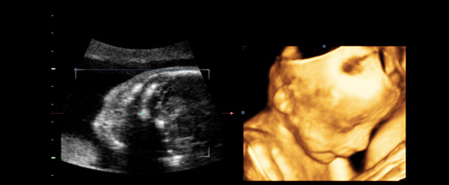

四维彩超是孕期排畸检查较为先进的一项内容,不仅可以看见宝宝在妈...

四维彩超相较于二维、三维B超而言,存在很大的优势,这些都是二维、...

对于孕妈妈来说,四维彩超已经不再是一个陌生的名词。但是,对于二维...

随着四维彩超的问世,很多孕妈妈也不再热衷与三维彩超,四维彩超拥有...